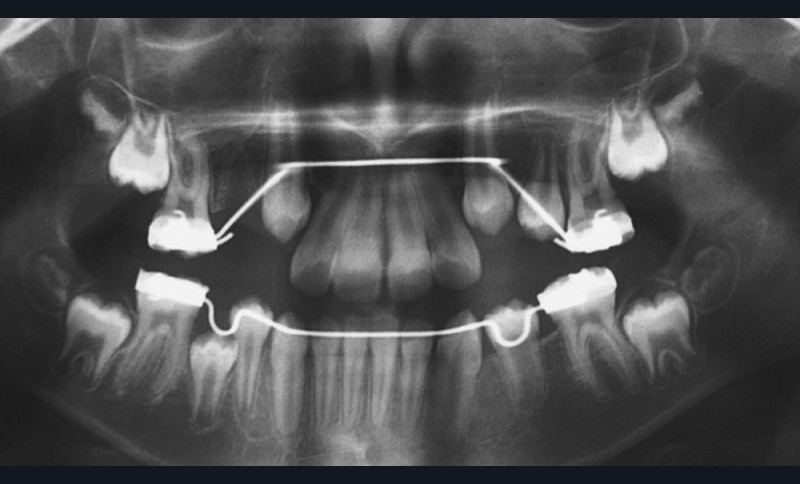

Lina, 8 ans et 5 mois, nous est adressée en consultation d’orthodontie dans le service de médecine bucco-dentaire de l’Hôpital Bretonneau en transfert avec absence des 2 prémolaires du secteur 1, alors que 44 et 45 sont présentes et que cette dernière manque de place pour faire son évolution sur l’arcade (fig. 1 et 2).

Un bilan radiologique 3D (Cone Beam CT) est prescrit dans le but d’évaluer, avec l’équipe de chirurgie du Dr Jean-Luc Charrier (Hôpital Bretonneau), la possibilité de transplantation d’une prémolaire du secteur 4 vers le secteur 1 et de définir le meilleur transplant possible entre 44 et 45. Sont analysées les dimensions du site receveur ainsi que l’anatomie, la position et l’état de maturation radiculaire des prémolaires candidates à la transplantation (fig. 3).